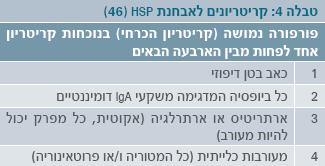

הקריטריונים לאבחנה מפורטים בטבלה 4.